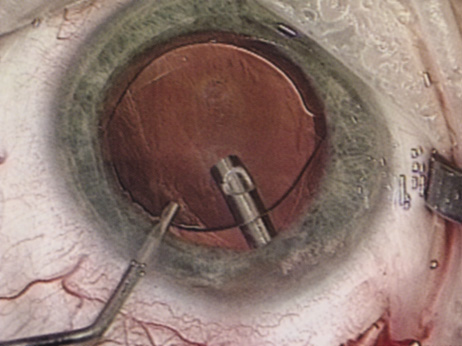

A mature cataract precludes visualization of the fundus. A B-scan ultrasonographic examination provides a real-time, two-dimensional (2D), cross-sectional image of the globe along the marked axis of the probe (Fig. 3). Cataracts are more common in patients with chronic retinal detachment, prior trauma, or intraocular tumors; therefore, a B-scan study is helpful in excluding structural posterior segment pathology before surgery on a mature cataract. Although a negative result to B-scan evaluation is reassuring, the surgeon should remember that it does not predict postoperative visual outcome. The B-scan can be thought of as a picture of Cincinnati from an airplane; the office buildings may all be standing, but you cannot tell whether the people in them are working.

Fig. 3. This B-scan ultrasound shows a normal looking posterior pole, without retinal detachment or intraocular mass. The vitreous cavity is echo lucent.